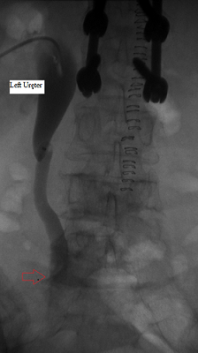

Left ureter before ballooning

Published July 12, 2014 at 198 × 353 in Bilateral insertion of nephroureteral stents after balloon dilation of malignant obstruction of the distal ureters. Ken U. Ekechukwu, MD, MPH, FACP..